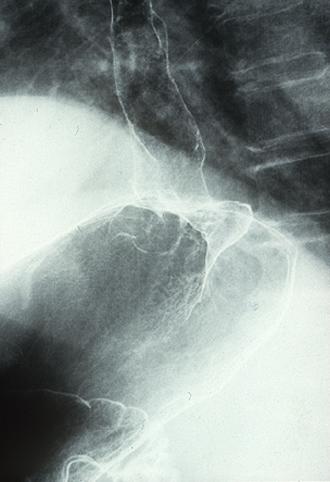

Cáncer Mucoso, que presenta la infiltración difusa en el esófago (tipo 4)

[Image-ID:8408]

Tumor Epitelial Maligno/Carcinoma Mucinoso

esófago/mas de dos

Rayos X

Tipo 4(Tipo difusamente infiltrado)/

40 -

s(a)